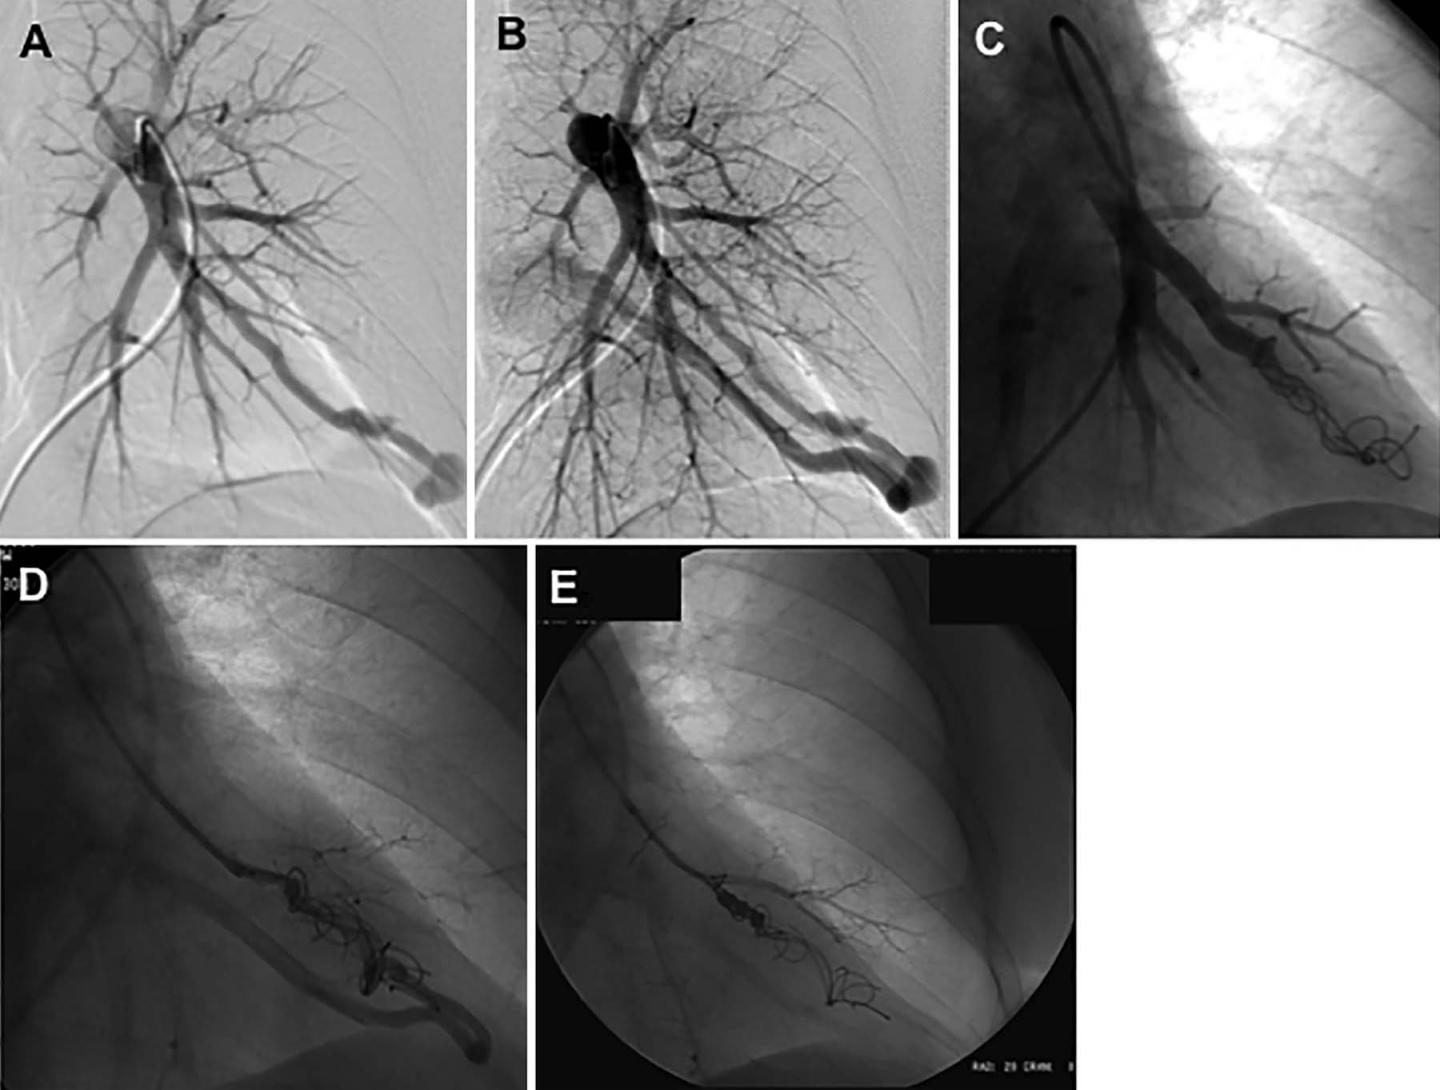

image: Images in a 52-year-old woman with hereditary hemorrhagic telangiectasia demonstrating on left pulmonary artery angiogram an arteriovenous malformation (AVM) at, A, B, the left base. C, Selective angiogram after embolization of the AVM by using coils. D, E, Angiogram shows embolization for persistence treated with repeat embolization performed 2 years after initial embolization.

In the embolization procedure, a catheter is threaded from a large blood vessel in the leg to the site of the PAVM. A small coil is then inserted to block the PAVM. The procedure is highly effective, but the PAVMs will persist in some patients.